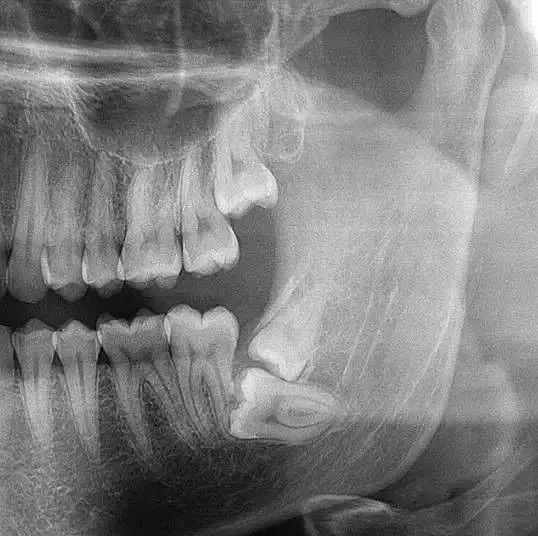

埋伏阻生牙

智齿俗称尽头牙,一般长在牙槽骨里,有的正常萌出,有的埋伏在牙槽骨里部分萌出或完全没有萌出。所以,拔除智齿需要拍全景片,医生才能看清楚牙齿长势、牙根位置以及和面部神经的距离!